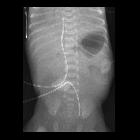

Premature

newborn after umbilical arterial catheter placement. AXR AP shows an umbilical arterial catheter whose tip projects inferiorly over the left external iliac artery. The tip of the umbilical venous catheter is at the cavo-atrial junction.The diagnosis was umbilical arterial catheter malfunction with malposition of the tip in the left external iliac artery.